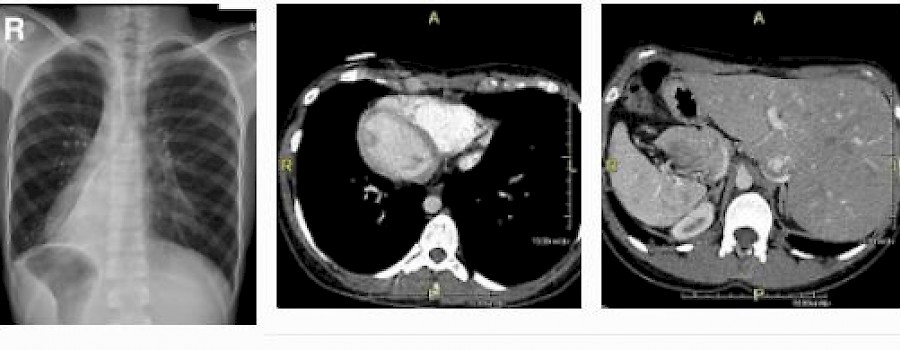

Bild links: Thorax pa bei Situs Inversus totalis. Das Herz befindet sich auf der rechten Seiteage des Herzens

Bild links: Thorax pa bei Situs Inversus totalis. Das Herz befindet sich auf der rechten Seiteage des Herzens

Bild mitte: Situs inversus in einer CT-Aufnahme des Brustkorbs: Das Herz befindet sich rechts

Bild rechts: Bauchaufnahme desselben Patienten: Die Leber ist links zu erkennen.